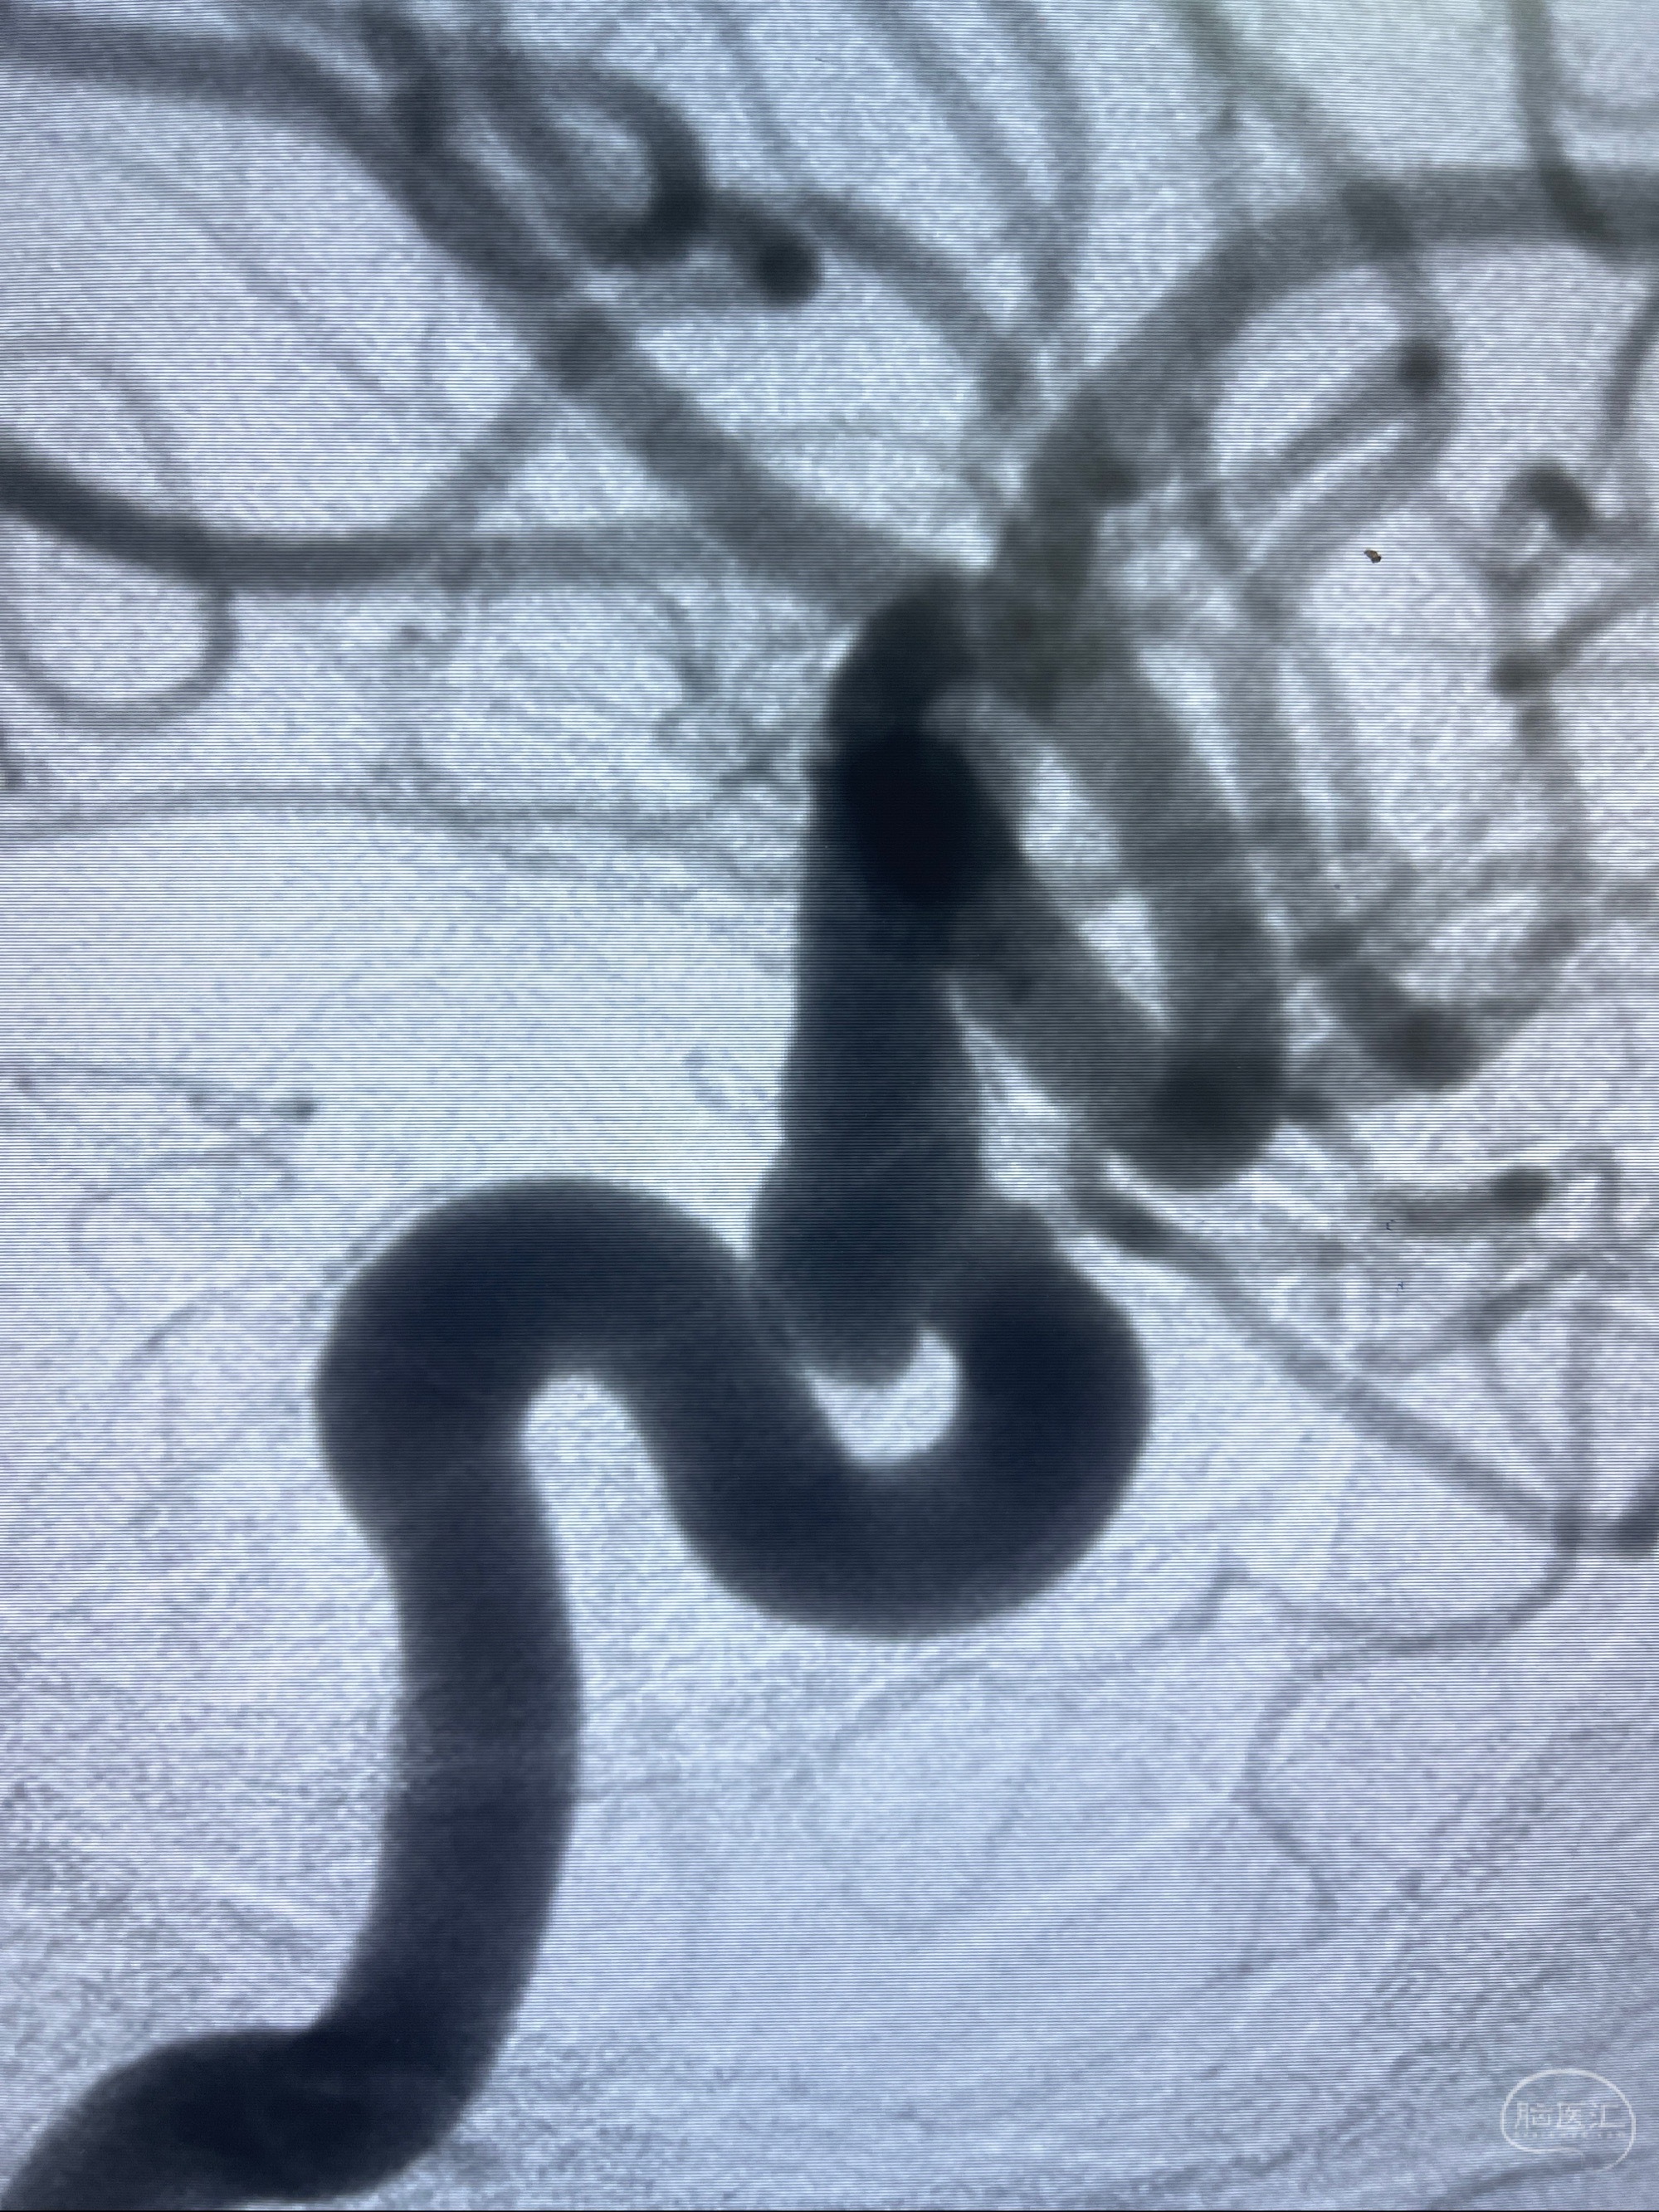

CTA示:右侧颈内动脉C6段见指向下方的突起,余左侧颈内动脉、双侧椎动脉、大脑前动脉、大脑中动脉、大脑后动脉及基底动脉走形正常,未见明显扩张及狭窄,局部未见明显瘤样扩张。

2023-07-27全脑血管造影:双侧颈内动脉眼动脉段动脉瘤,右侧较大

2023-08-01全麻下行双侧颈眼动脉瘤支架辅助栓塞

- pipeling4.5-20mm

- pipeline 4.0-20mm